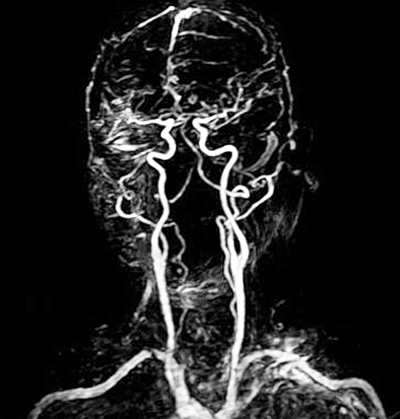

核磁共振的另一特点是流动液体不产生信号称为流动效应或流动空白效应。因此血管是灰白色管状结构,而血液为无信号的黑色。这样使血管很容易与软组织分开。正常脊髓周围有脑脊液包围,脑脊液为黑色的,并有白色的硬膜为脂肪所衬托,使脊髓显示为白色的强信号结构。

磁共振成像无骨性伪影,可随意作直接的多方向(横断、冠状、矢状或任何角度)切层,对颅脑、脊柱和脊髓等的解剖和病变的显示,尤优于CT,磁共振成象借其“流空效应”,可不用血管造影剂,显示血管结构,故在“无损伤”地显示血管(微小血管除外),以及对肿块、淋巴结和血管结构之间的相互鉴别方面,有独到之处。磁共振成像有高于CT数倍的软组织分辨能力,它能敏感地检出组织成分中水含量的变化,故常可比CT更有效和早期地发现病变。近年来,磁共振血流成像技术的研究,使在活体上测定血流量和血流门控的使用,使磁共振成像能清楚地、全面地显示心脏、心肌、心包以及心内的其他细小结构,为无损地检查和诊断各种获得性与先天性心脏疾患(包括冠心病等),以及心脏功能的检查,提供了可靠的方法。随着各种不同的快速扫描序列和三维取样扫描技术的研究和成功地应用于临床,磁共振血管造影和电影摄影新技术已步入临床,且日臻完善。最近又实现了磁共振成像和局部频谱学的结合(即MRI与MRS的结合),以及除氢质子以外的其他原子核如氟、钠、磷等的磁共振成像,这些成就将能更有效地提高磁共振成像诊断的特异性,也开阔了它的临床用途。

2、头颈部 MRI对眼耳鼻咽喉部的肿瘤性病变显示好,如鼻咽癌对颅底、颅神经的侵犯,MRI显示比CT更清晰更准确。MRI还可做颈部的血管造影,显示血管异常。对颈部的肿块,MRI也可显示其范围及其特征,以帮助定性。